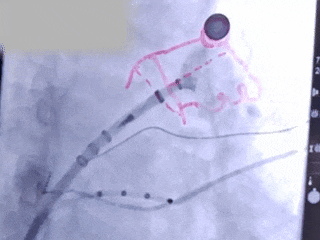

造影

测量压缩比

压缩比10%

造影评估后封堵器释放

Lefort封堵器评估符合PASS原则,释放封堵器,封堵器位置稳定且未见残余漏

术前结合CT以及术中造影评估左心耳开口23.27mm,深度22.45mm,心耳内部空间较大,且患者全身情况良好,可较配合局部麻醉手术,采用极简式封堵术安全可行。术中考虑心耳开口和深度充足,可利用心耳空间进行退鞘释放封堵器,使封堵器完全封堵左心耳。术中采用半回收方式调整封堵器在心耳内的位置形态,确保封堵器放置位置合适,且牵拉稳固,术后封堵器形态完整,未见残余漏。本病例展开后即刻造影,平口封堵,上下缘不留残腔。封堵器压缩比为10%,压缩合适,术中符合PASS原则,释放封堵器,术后封堵器稳固锚定在心耳壁,封堵器与心耳紧密贴合,无过度扩张风险,显著提升封堵完整性。